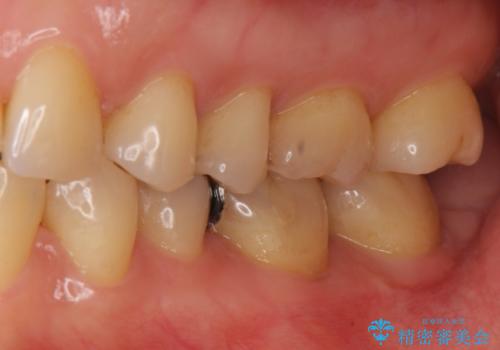

目立つ銀歯を全て白く セラミックで虫歯治療

- 銀の詰め物が気になるとのことで来院。

2本隣り合っているつめものを、同時にやりかえをしました。

- 14万円(左下5・左下6 emaxプレスインレー 7万円 x 2)費用は治療当時の料金となります

向かい合う銀歯を同時にやり変えることで、コンタクト(歯と歯の間の形)を理想的に仕上げることができ、ものも挟まりにくいように仕上げることができます。